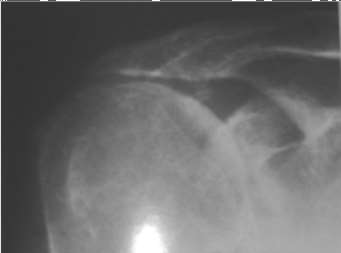

ORTHOPEDIC MCQS ONLINE BANK OITE 22 FOR OITE 22 FIGURES CLICK OITE22FIG 02.1 answer back A 30-year-old patien…